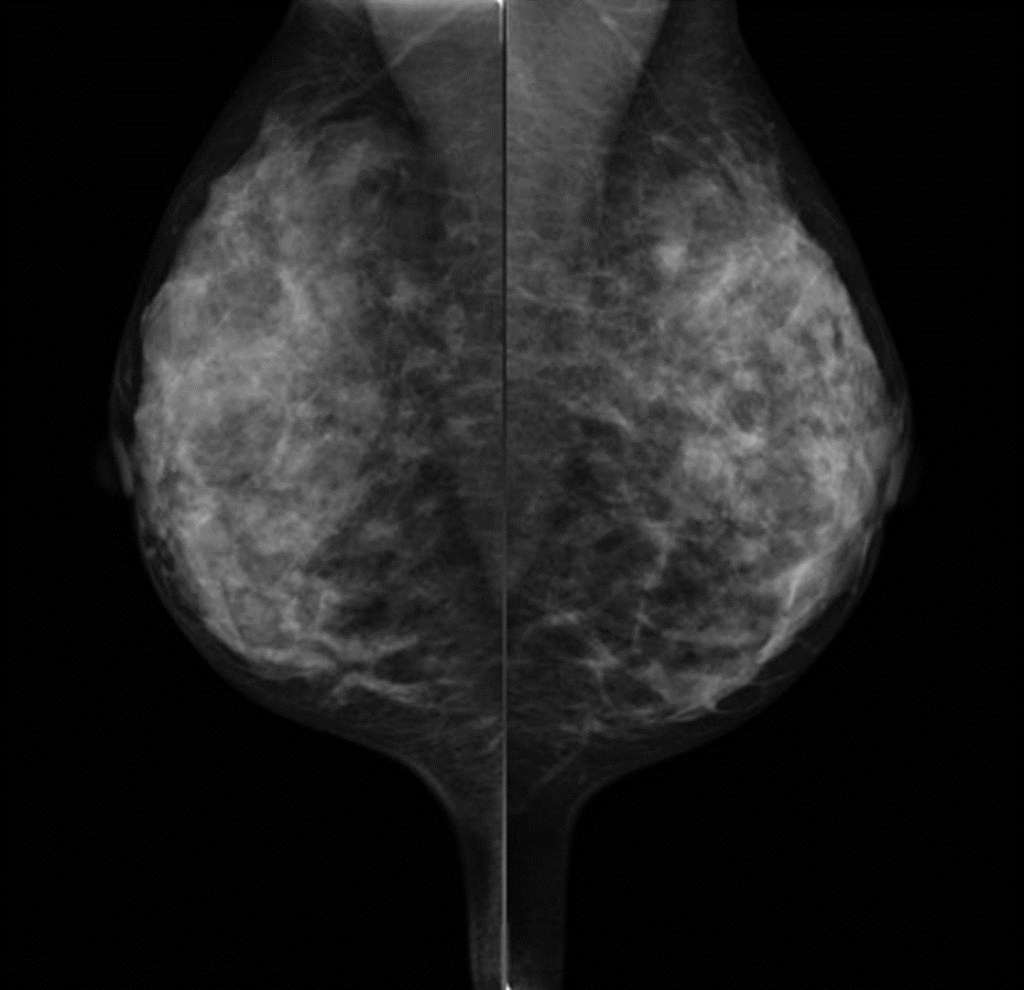

マンモグラフィ検査

マンモグラフィ検査

マンモグラフィ装置

マンモグラフィとは乳房のX線撮影のことです。乳癌の初期症状である小さな石灰化を写し出せるのが大きな特徴です。触診では触れない小さな乳がんを写し出すことが出来ます。

検査は上半身の衣類を脱いでから、専用の検査着に着替えて行います。乳腺組織を見やすくするために、乳房を圧迫板で片方ずつ挟んで撮影します。標準撮影は、左右の乳房を上下方向と斜め横方向の4回で検査時間は 10 分程度です。

圧迫伸展して撮影することで乳腺組織や病変の重なりが減り、正しい診断を行いやすくします。痛みをともなう場合もありますが、X線被曝量を減らす効果もあります。痛みが強いときは加減しますので、遠慮なくおっしゃってください。生理が終わってから1週間くらいの間は、乳腺が柔らかいので、痛みが減る傾向があります。

乳房トモシンセシスについて

トモシンセシス撮影とは、マンモグラフィの 3D 画像のことです。従来のマンモグラフィと同様に、乳房を挟んだ状態で複数の方向から撮影を行い、1mmスライスの細かい画像を作成します。通常のマンモグラフィに追加して撮影することで、乳腺の重なりによって発見しづらかった病変が見つけやすくなります。厚みのある乳房内の重なりを減らすことにより、乳腺の奥の病変の観察がしやすくなります。一回の圧迫時間は 10〜15 秒程度で、ぶれないように息を止めて撮影します。

2D撮影

トモシンセシス撮影